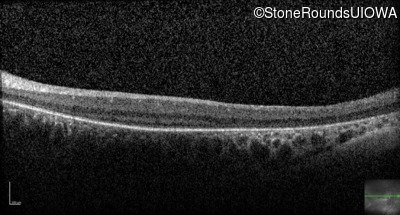

Optical Coherence Tomography - Left - Light Perception

Exemplar